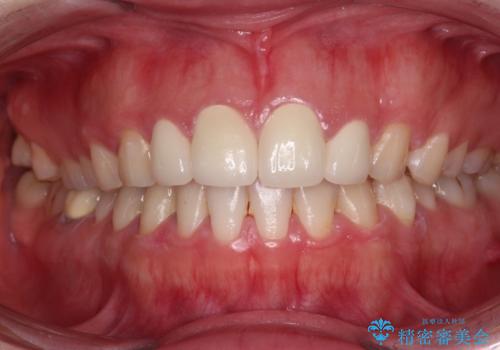

前歯の捻れは、オールセラミッククラウンよりも矯正治療による改善の方が、歯を削らなくて済むためお勧めとなります。

しかし、矮小歯の改善はオールセラミッククラウンでの補綴治療が必要であり、幅径のバランスを取る必要があるため、4前歯の補綴治療を選択しました。